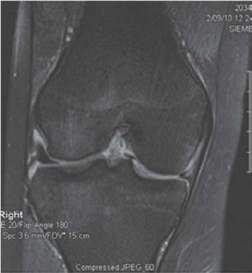

KNEE Structured oralexamination question6: Anterior cruciate ligament (ACL) and posterior cruciate ligament (…